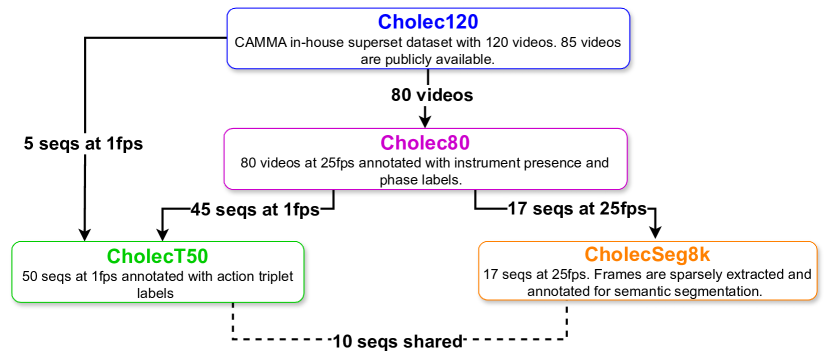

The CholecInstanceSeg dataset is curated using frames extracted from three existing laparoscopic cholecystectomy datasets: Cholec80 [12], CholecT50 [13], and CholecSeg8k [11], containing a total of 85 image sequences. These datasets are publicly available subsets of the in-house Cholec120 dataset [15] from the CAMMA research group at the University of Strasbourg. The interrelation between these datasets is illustrated in Figure 1.

A visual representation of dataset partitions in CholecInstanceSeg can be seen in Figure 2.